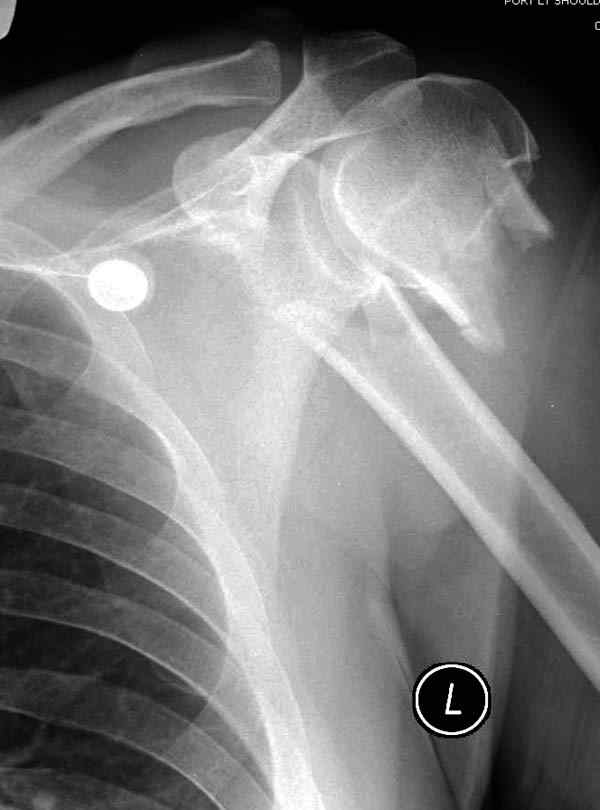

Здесь пример открытой репозиции 57 летнего с переломом плеча (1,2) смещение обнаружено на интероперационном снимке. При нормальной прямой проекция (3) угловое смещение обнаружили в аксиальной проекции (4)

После устранения смещения пластина установлена выше (5,6,7) и финальные снимки (8,9,10)

Хотя в данном случае после такого остеосинтеза трудно угадать, что будет в ближайшее время, все зависит от желания и активности больной. Отсутствие позитивной динамики в амплитуде движении и болевой симптом является показанием к ре-остеосинтезу.